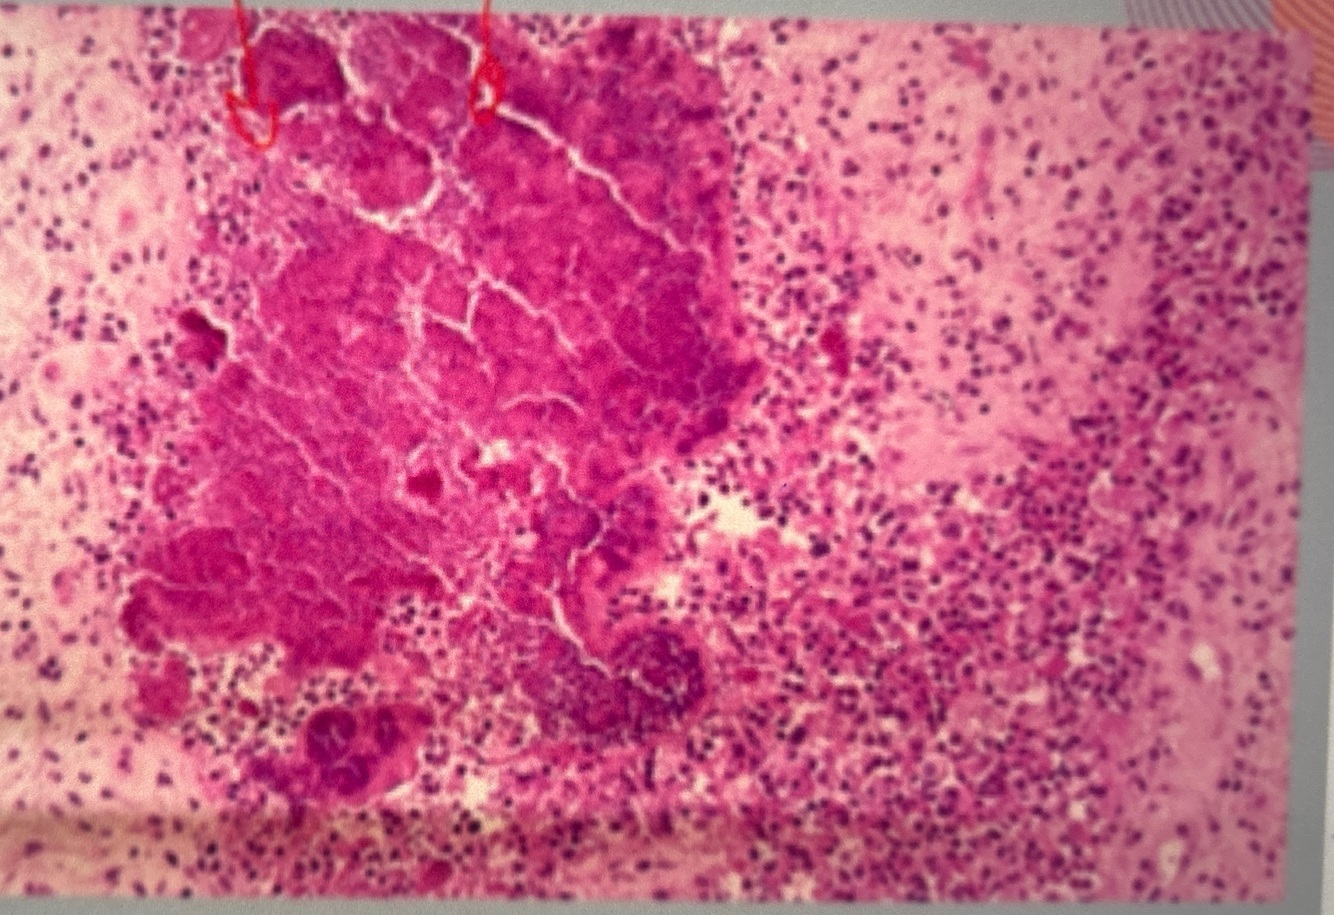

Qual achado da imagem no círculo ? Diagnóstico?

Leveduras agrupadas e em aspecto catenular

Infiltrado granulomatoso

Lobomicose